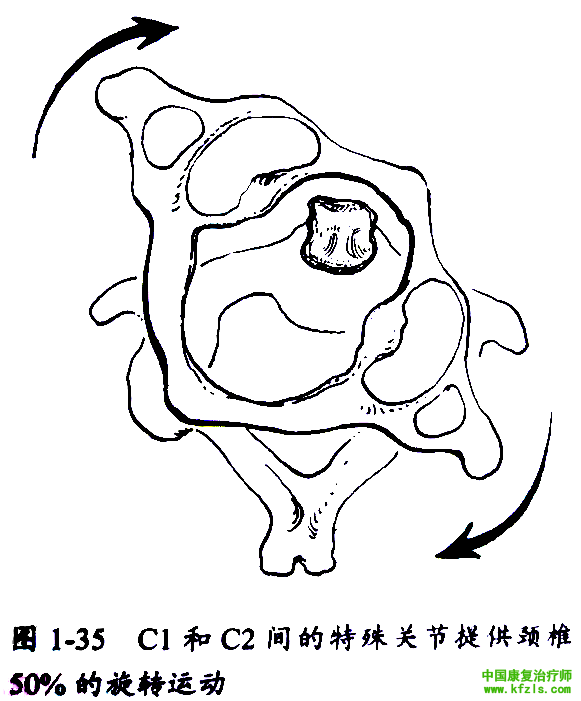

C5~6节段与其余颈椎节段相比,活动度较大(除枕骨与C1及C1和C2间的特殊关节) (图1-34和1-35),而较大的活动度导致相应节段发生退变、椎间盘突出及骨关节炎几率增大。